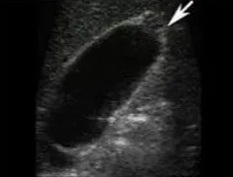

图2,腺肌增生症

腺肌增生症一般是胆囊壁的一种非炎症也非肿瘤性的良性病变。

超声表现为胆囊壁增厚,可呈弥漫型、节段型或是底部的局限增厚隆起。

其中底部出现腺肌增生症比较常见。